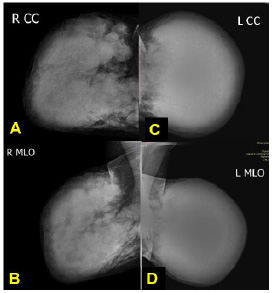

Fig. (3).

Mammography: CC and MLO (A, B) views of both breasts show extremely dense fibro glandular tissue with multiple different sizes of hyper-dense obscured margin matted masses at the right breast region. (C) The left breast shows a large, ill-defined block of hyper-dense mass that was very firm at the examination and even was non-compressible during the mammographic procedure; no visible normal fatty tissue, no associated microcalcification, and no nipple abnormalities were seen. (C,D) Bilateral axillary lymph nodes were noted to be round to oval in shape with loss of fatty hilum, categorized as BIRADS 4c.

The mammography (Fig. 3A-D) and ultrasound examination (Figs. 4A-C, 5A-B) showed BI-RADS 5. It was very suspicious of an aggressive malignant process, given the identification of multiple matted masses with increased vascularity and bilateral lymphadenopathy. In light of these findings, multiple core needle biopsies from both breasts and fine needle cytology from the axillary LN were strongly recommended to confirm the diagnosis. Figs. (6A-D and 7A-D) highlight histopathological findings.